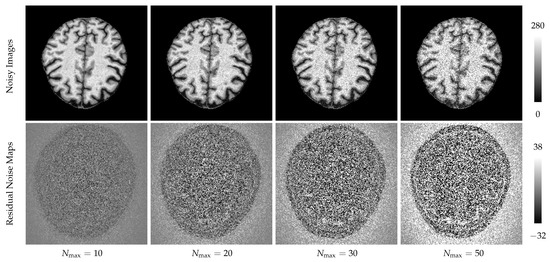

And next, for testing the segmentation performance under noise corruption, we add spatially varying Rician noise to MR magnitudes. To achieve this, we firstly simulate phase maps according to the literature [33]; and next, we generated both real and imaginary components and added spatially varying Gaussian noise to each component separately. The noise level follows the 2D Gaussian distribution in the same manner as the literature [34]. Based on the noisy components, we eventually generate the noisy magnitude with Rician noise using the simple sum of square (SoS) image reconstruction manner [35]. More specifically, we added 4 levels of spatially varying Gaussian noise to the complex components, with maximal noise levels N max = { 10 , 20 , 30 , 50 } . The noisy images and residual noise maps are shown in Figure 3.

Figure 3. After added Rician noise to the ground truth data, we can see in the first row that the image is corrupted by the noise in different levels, denoted by N max . After subtracting the noisy image from the ground truth, we derived residual maps of Rician noise shown in the second row. Because the Rician noise is signal dependent, we can see apparent content textures in the residual noise maps.